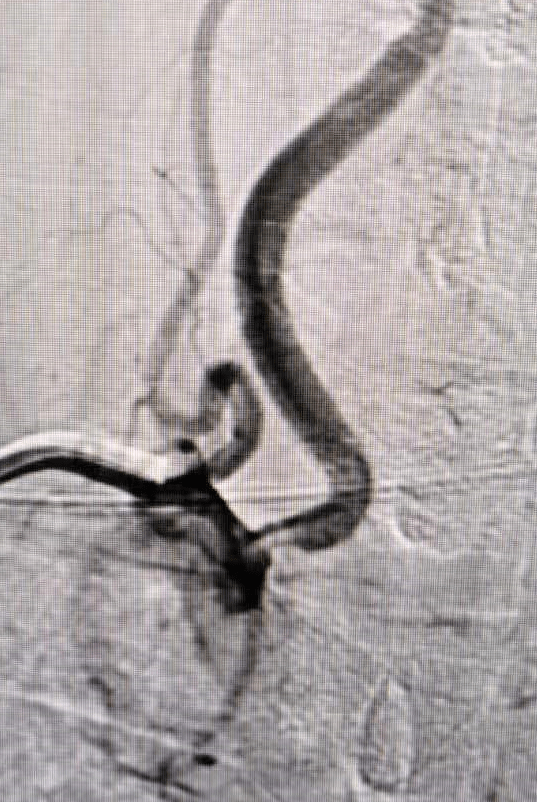

患者曹某,男,60岁。因言语笨拙伴右侧肢体活动不灵3天入院。入院诊断为:脑梗死。7月1日经桡动脉脑血管造影显示:左颈内动脉闭塞、左椎动脉闭塞、右椎动脉开口部位重度狭窄。考虑到患者双侧椎动脉一侧闭塞,一侧严重狭窄,打开狭窄一侧血管对改善后路供血意义重大。向患者及家属交代病情后,其同意我们的治疗方案,对我们的技术充满信心。其后我们认真测量狭窄部位各项指标,选择合适的球扩支架,经桡动脉入路为我们提供了最直接、稳定的手术路径,顺利的到达狭窄部位后释放支架。造影见狭窄明显改善,手术在半小时内获得成功。

此例手术的成功,标志着我院具备了独立开展神经介入治疗手术的能力,增强了团队的信心。相信在院领导的大力支持下,在患者的信任下,我院的神经、周围血管及综合介入治疗中心必将成为医院的又一特色专科,不断发展壮大,更好的护卫人民健康!